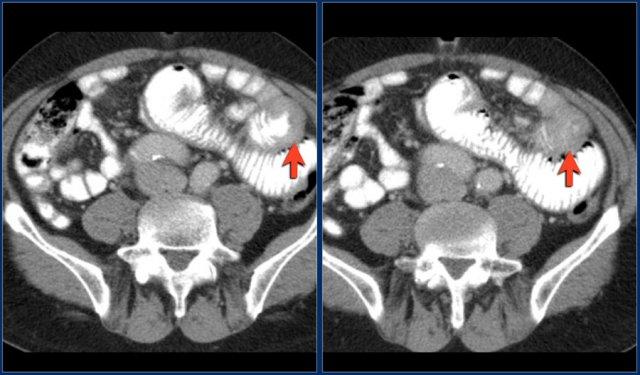

Các hình ảnh cho thấy một khối phát triển theo chu vi với bờ dạng vai.

Ung thư biểu mô tuyến kích thước lớn có thể bắt chước hình ảnh u lympho như trong trường hợp này.

Các hình ảnh cho thấy một khối không đều ở đoạn gần hỗng tràng.

Mặc dù là khối phát triển theo chu vi với kích thước lớn, lòng ruột không bị tắc nghẽn.

Có một khối hạch bạch huyết tập hợp lớn giảm tỷ trọng ở mạc treo lân cận, phù hợp với di căn hạch bạch huyết hoại tử (hình dưới).

Kết quả giải phẫu bệnh xác nhận là ung thư biểu mô tuyến, nhưng các dấu hiệu này cũng có thể rất phù hợp với u lympho.

Đây là hình ảnh nội soi của khối u.